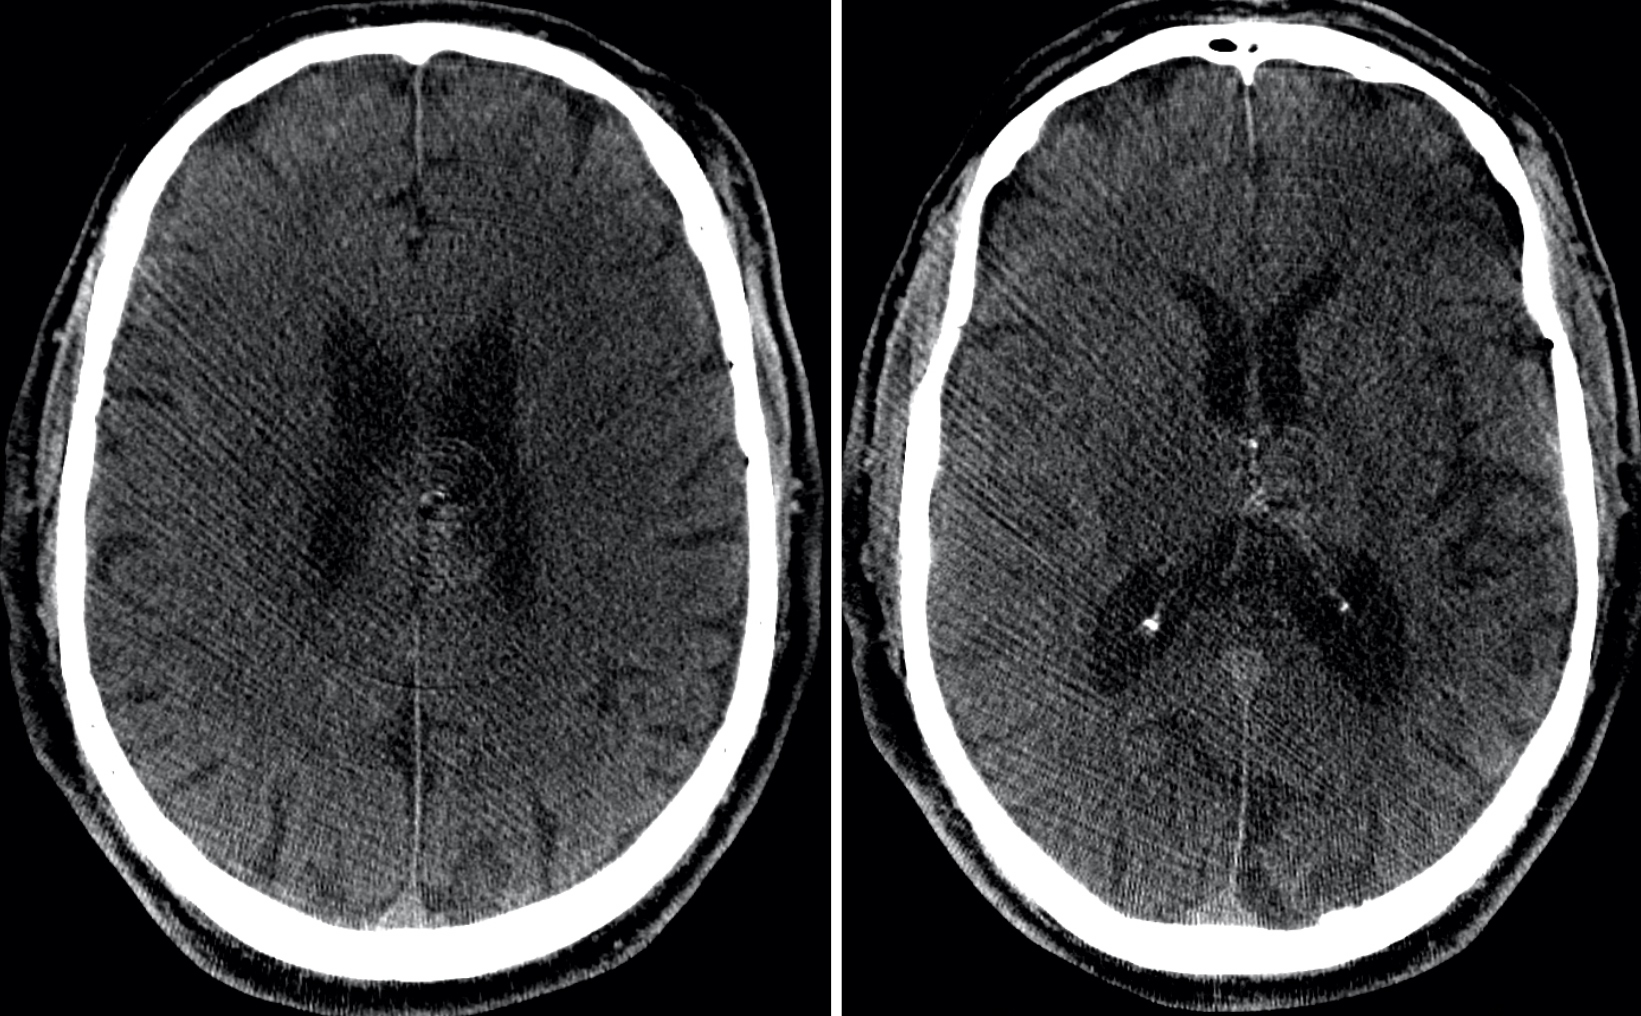

The patient was transferred to Swedish Medical Center within 60 minutes of the previous CT, which was visualized remotely with AI technology (Figure 2).

The patient was sent DTA and a Sine Spin head CT was done (Figure 3). Thrombolysis in cerebral infarction (TICI) 3 was achieved after 1 pass (Figure 4). Time from door to recanalization was 43 minutes. Figure 5 shows the patient’s MRI after 24 hours.